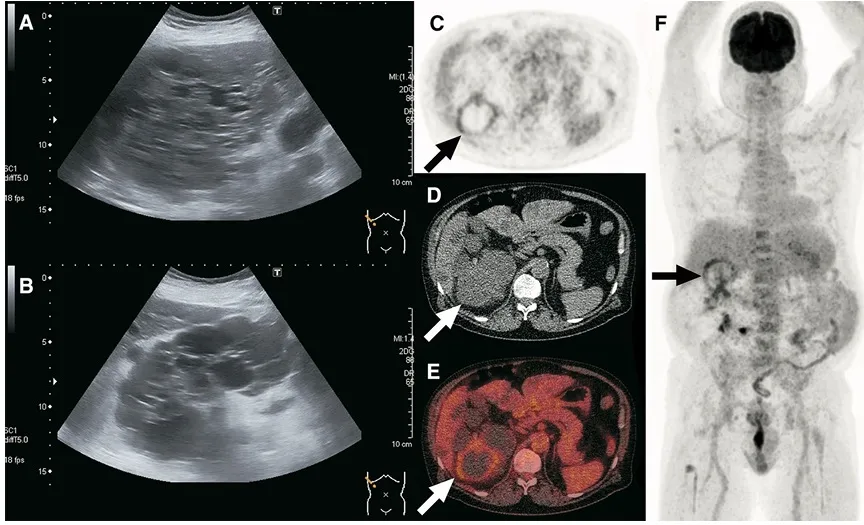

Infecção de Cistos na DRPAD — abordagem prática para diagnóstico